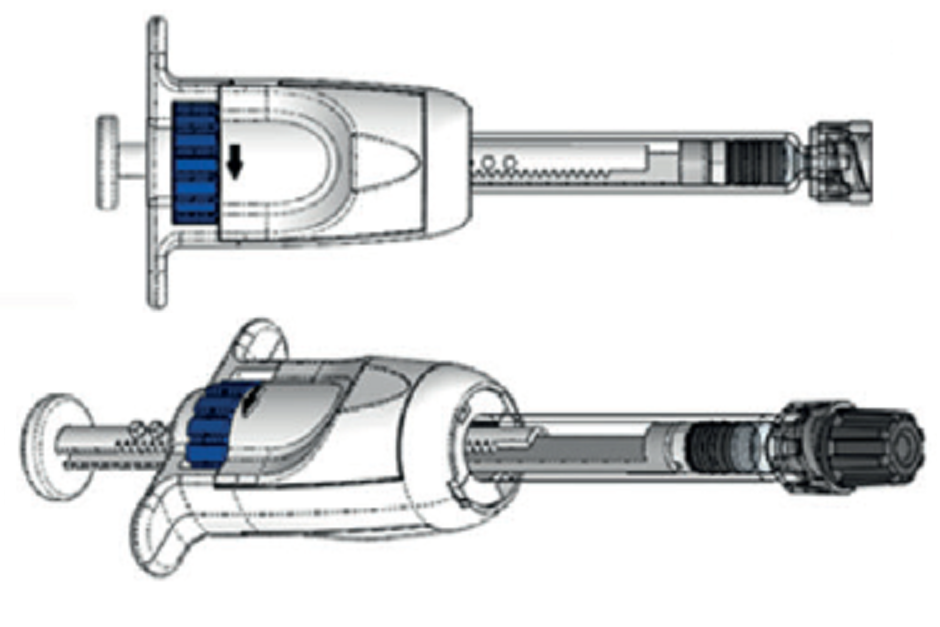

Figure 2: The Microliter Dosing Syringe (MDS) incorporates standard prefillable syringes, shown here with various 1 mL long prefillable syringes.

SM Santen’s core expertise is not in injectable drug delivery devices and associated primary packaging. We constantly evaluate external partnerships that offer new technologies that will help our products in tiers. Microlitre dosing serves as an enabling technology when the existing commercially available syringes do not meet our criteria for low-volume accurate dosing. When trying to bring a best-in-class therapeutic onto the market, the delivery plays a big role. The MDS format (Figure 2) can be a key differentiator with a competitive advantage. In addition, as it takes a long time to ultimately commercialise a drug product, a device as a lifecycle-management tool becomes very critical for us. MDS can help us manage the lifecycle of the drug product as well. Finally, our core expertise lies in drug product development and not device development, so we decided to look for external partners who can help us build a prefilled syringe-based platform.

GS The MDS platform can be made available as a prefilled syringe format or so that drug can be filled from a vial, and its injection dose volume can be preset by the manufacturer, or set by the user. This gives four different combinations of configurations (Figure 4). The MDS in its non-prefilled configuration enables a prefillable syringe to be paired with a vial-filled drug. We have initiated submission of the MDS for US FDA 510k premarket clearance. expect in 2020 the MDS will be available for use in drug clinical trials or drug commercial sales.

Figure 4: The MDS platform can be made available in four different configurations.